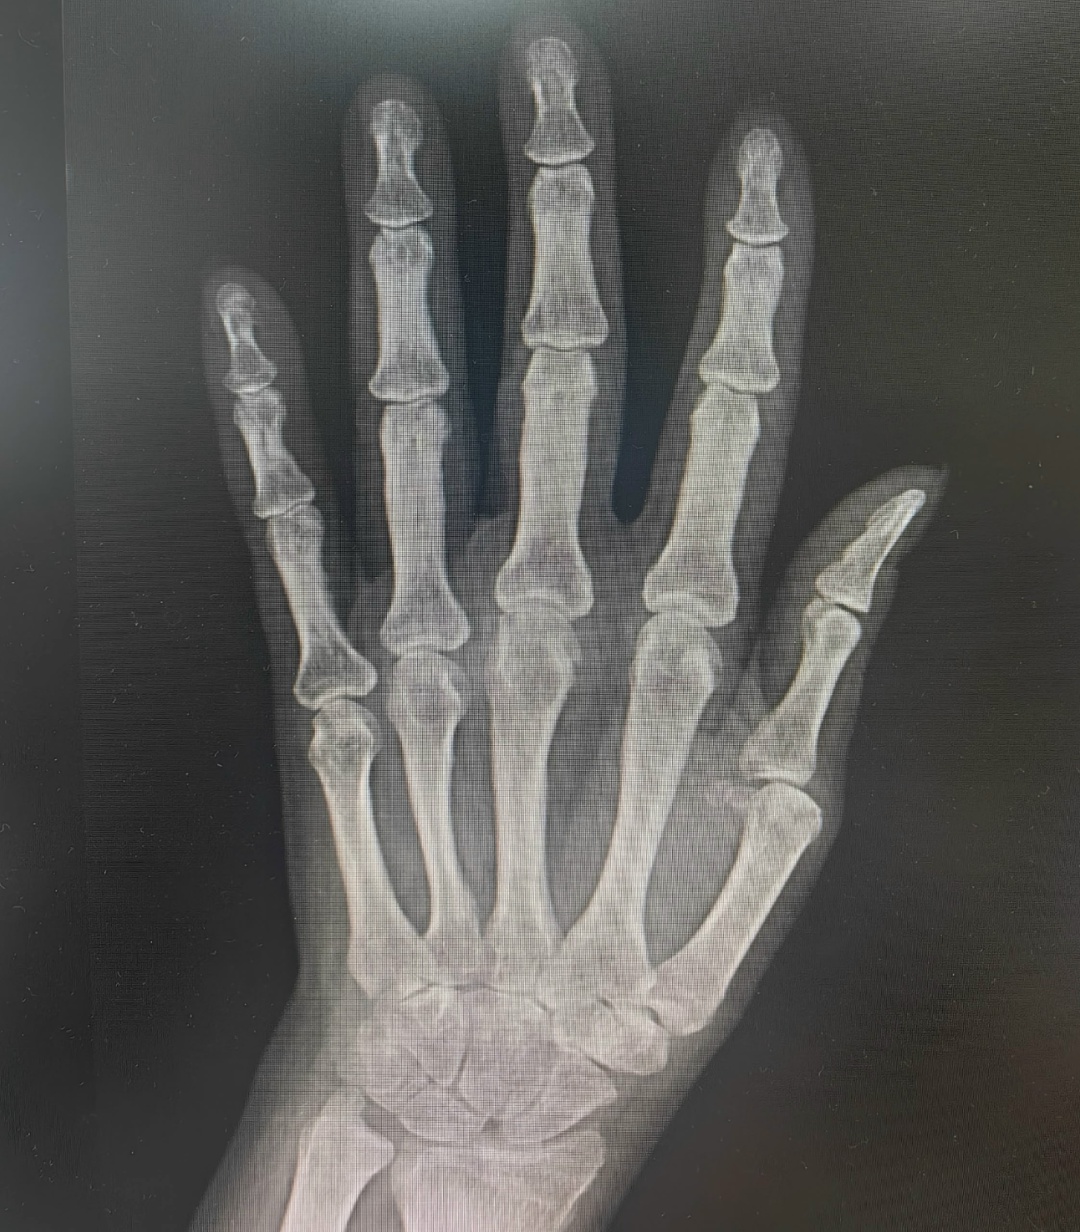

На рассмотрении экспертов молодая пациентка с сердечно-сосудистыми осложнениями на фоне иммуновоспалительного заболевания.

Диагноз уточнен, терапия скорректирована, а пациентка маршрутизирована на проведение генно-инженерной терапии. 💉 В процессе терапии пациентка продолжит наблюдение врачами клиники 👨⚕️